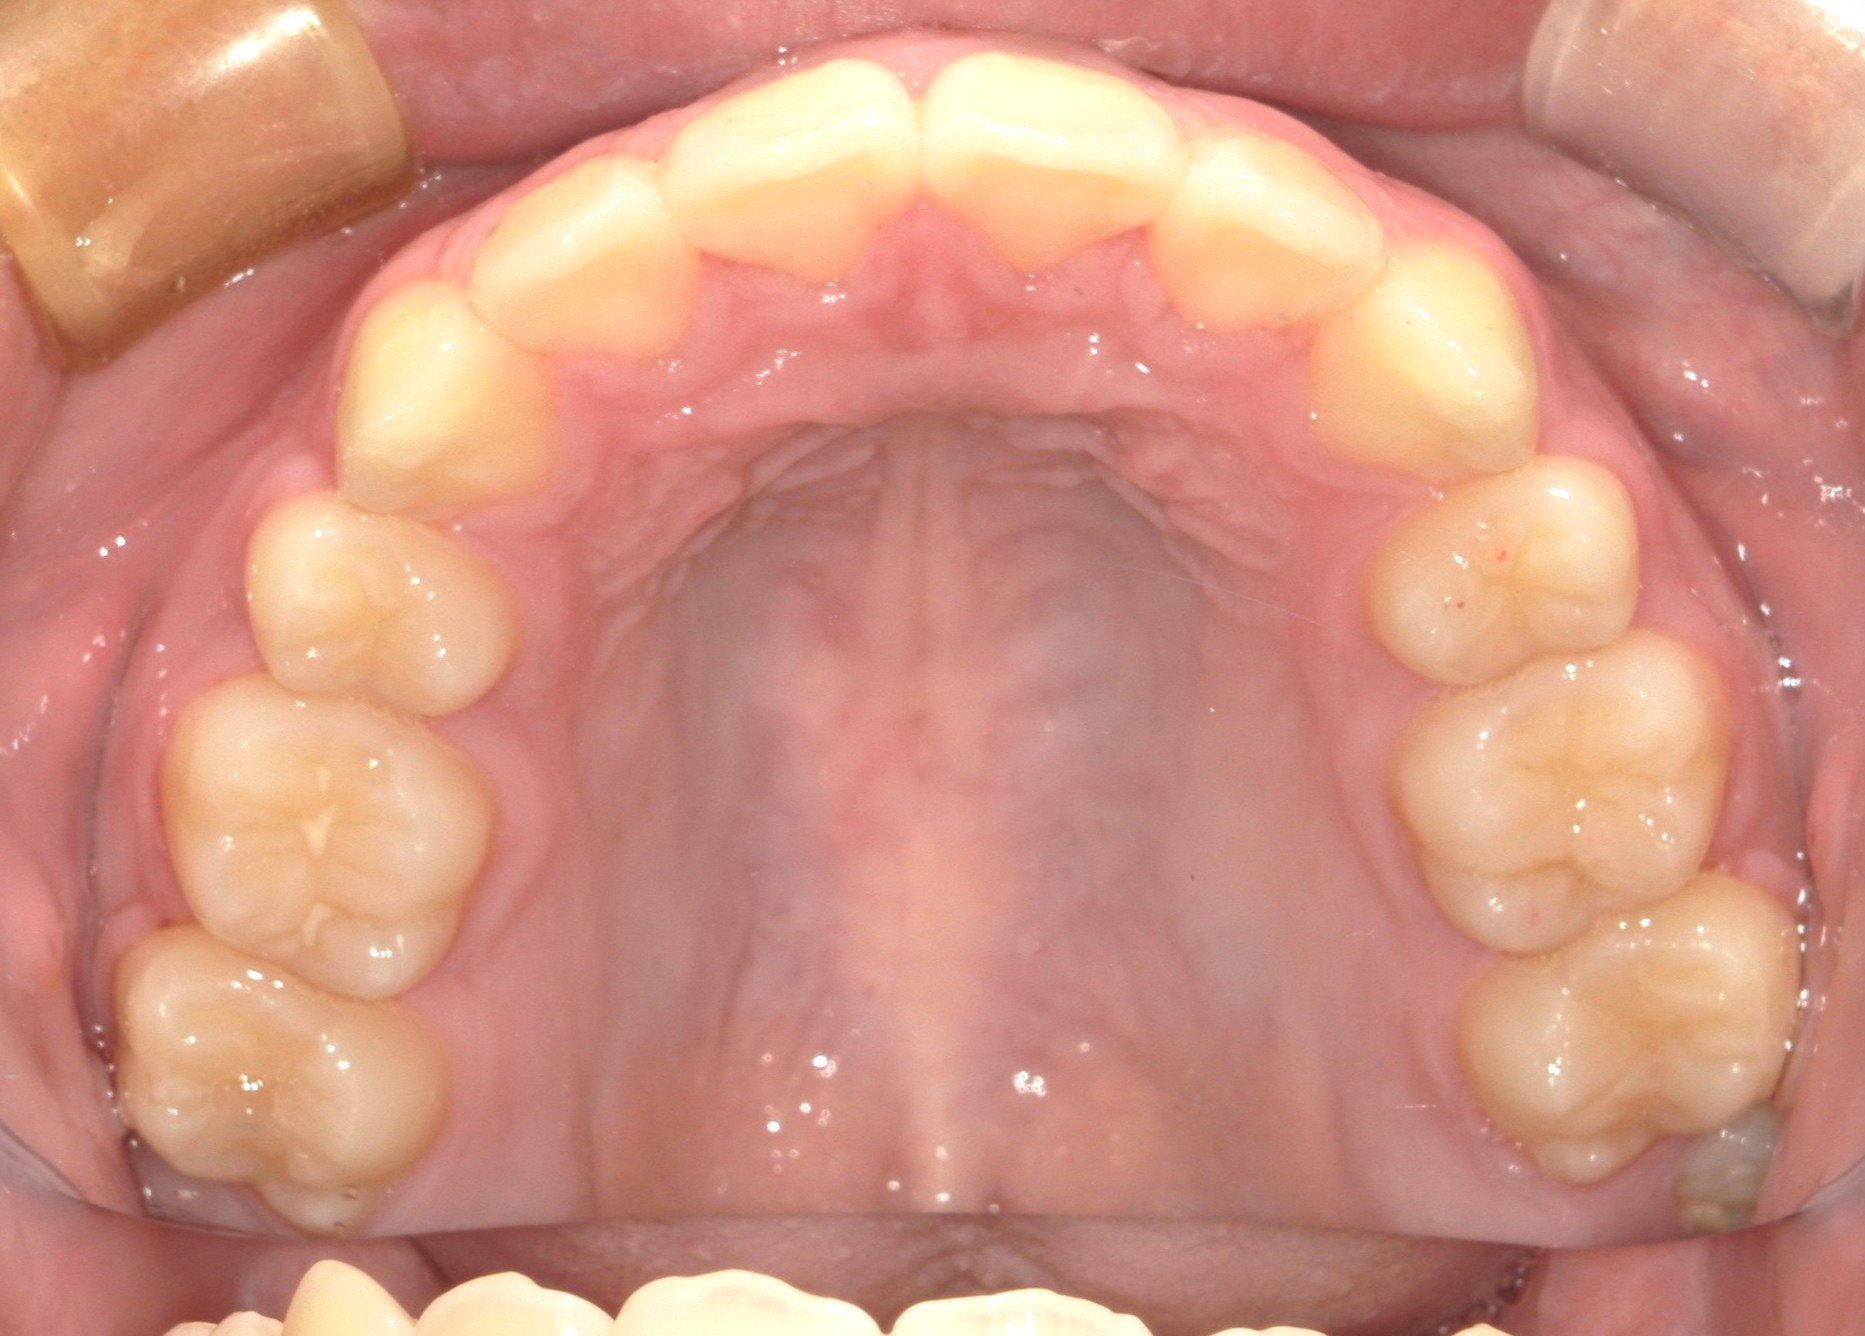

口内上

治療前

治療後